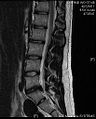

The majority of spinal disc herniations occur in the lumbar spine (95% at L4–L5 or L5–S1).[19] The second most common site is the cervical region (C5–C6, C6–C7). The thoracic region accounts for only 1–2% of cases. Herniations usually occur postero-laterally, at the points where the annulus fibrosus is relatively thin and is not reinforced by the posterior or anterior longitudinal ligament.[19] In the cervical spine, a symptomatic postero-lateral herniation between two vertebrae will impinge on the nerve which exits the spinal canal between those two vertebrae on that side.[19] So, for example, a right postero-lateral herniation of the disc between vertebrae C5 and C6 will impinge on the right C6 spinal nerve. The rest of the spinal cord, however, is oriented differently, so a symptomatic postero-lateral herniation between two vertebrae will impinge on the nerve exiting at the next intervertebral level down.[19]

Lumbar disc herniations occur in the back, most often between the fourth and fifth lumbar vertebral bodies or between the fifth and the sacrum. Here, symptoms can be felt in the lower back, buttocks, thigh, anal/genital region (via the perineal nerve), and may radiate into the foot and/or toe. The sciatic nerve is the most commonly affected nerve, causing symptoms of sciatica. The femoral nerve can also be affected and cause the patient to experience a numb, tingling feeling throughout one or both legs and even feet or a burning feeling in the hips and legs.[20] A herniation in the lumbar region often compresses the nerve root exiting at the level below the disc. Thus, a herniation of the L4–5 disc compresses the L5 nerve root, only if the herniation is posterolateral.